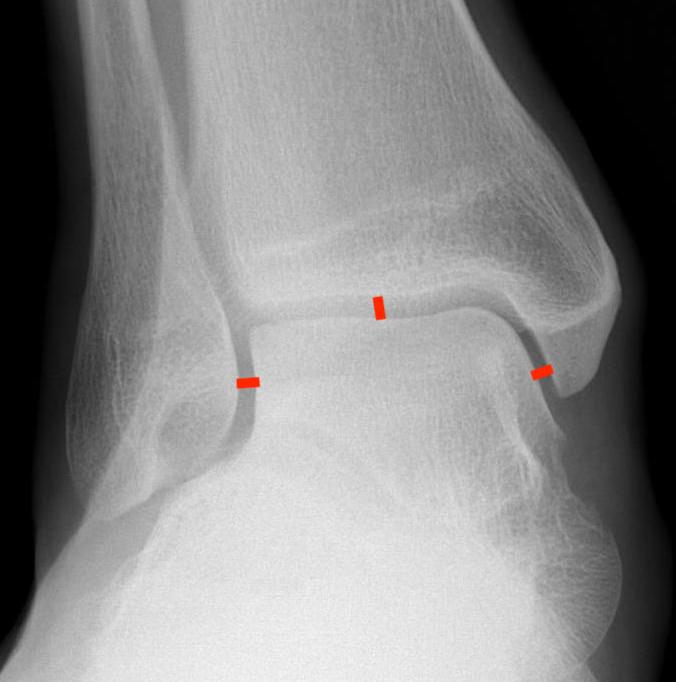

Increased tibio-fibular clear space  Overlap Increased medial clear space

Medial border of the fibula

Lateral border of the posterior tibia (incisura fibularis)

Measured 1 cm above the plafond

Overlap of the fibula and the anterior tibial tubercle

Medial talus to lateral medial malleolus

<5mm AP and mortise

> 6 mm AP view

> 1 mm mortise view

< 4mm

Equal to superior clear space

Syndesmotic injury Syndesmotic injury

Deltoid ligament injury

Lateral talar shift

Ankle AP Xray Syndesmotic Measurements Ankle Mortice Xray Syndesmotic Measurements Mortise